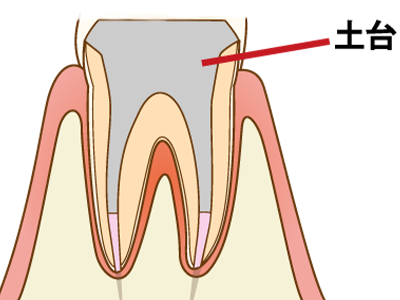

7 歯根にコアと呼ばれる土台(支柱)をたてて、バクテリアが内部に侵入しないよう完全に封鎖し、歯を被せる準備をします